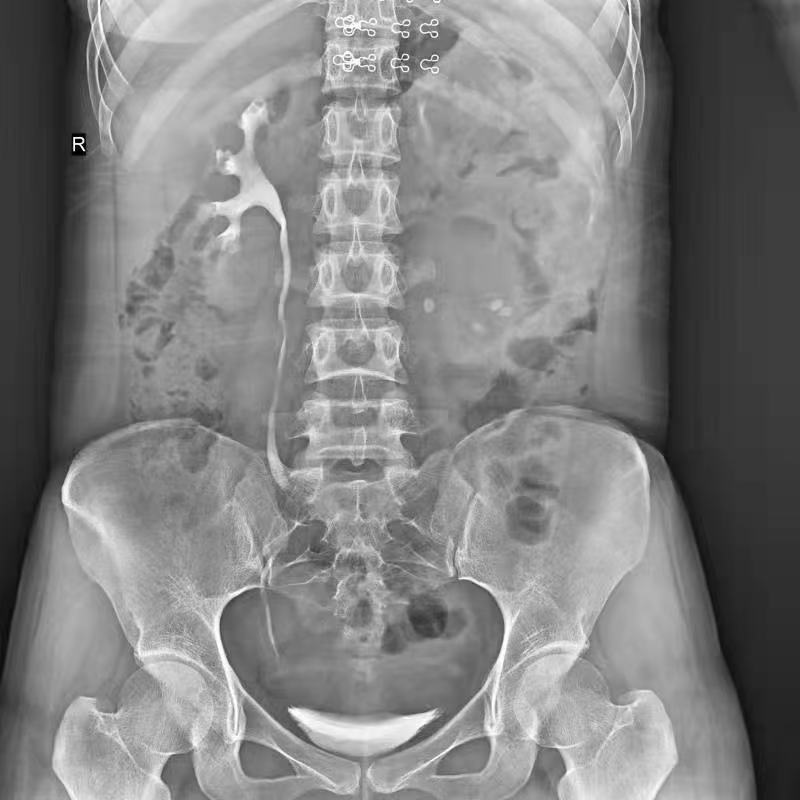

盆骨 (2)

腎盂造影